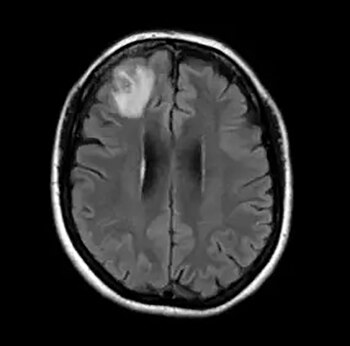

Una punción lumbar reveló niveles extremadamente altos de eosinófilos, un tipo de glóbulo blanco que combate infecciones parasitarias. Este hallazgo, junto con su historial reciente de viaje, permitió a los médicos identificar la causa: una infección por Angiostrongylus cantonensis, un parásito que afecta principalmente a las ratas, pero que puede transmitirse a los humanos a través de caracoles, babosas o alimentos contaminados con sus secreciones.

El doctor Joseph Zunt, neurólogo especializado en enfermedades infecciosas, explicó que la paciente sufría de meningitis eosinofílica, una inflamación de las membranas que rodean el cerebro y la médula espinal causada por este parásito. Según The New York Post, el diagnóstico fue posible gracias a la combinación de la punción lumbar y el análisis de su comportamiento y actividades durante su estancia en Hawái, donde esta enfermedad es un problema conocido.